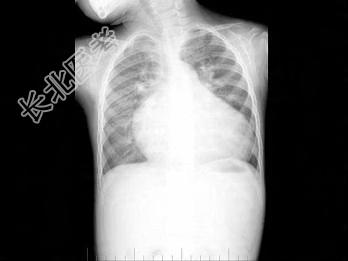

- 单项选择题男性,1岁零8个月, 生长发育差,易患呼吸道感染, 心悸气促,行心脏正、侧位片检查如图所示, 错误的是  (    )

A、正位示心影向两侧扩大,心尖左移

B、肺纹理增多

C、侧位示心前间隙变窄,心后食管前三角间隙消失

D、房间隔缺损

E、室间隔缺损